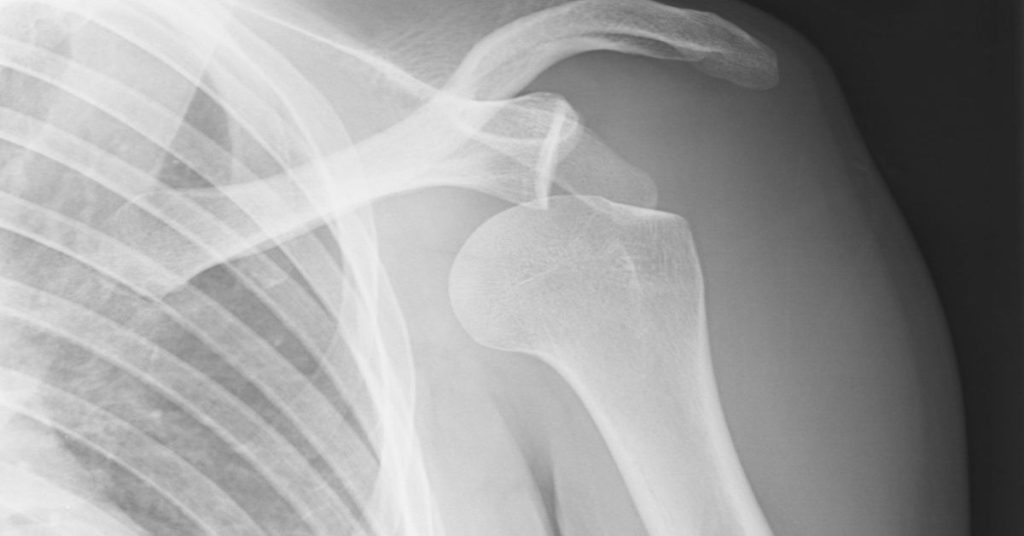

Tekrarlayan çıkıklar hastanın yaşam kalitesini düşürür. Kol yukarı kaldırıldığında kayma hissi yaşanabilir. Gece uykuda bile omuz yerinden çıkabilir. Özellikle genç ve aktif bireylerde tekrar oranı yüksektir. Sporcularda performans kaybı görülür. Bu durumda ileri tetkik yapılır. Manyetik rezonans görüntüleme ile bağ ve kemik yapıları değerlendirilir. Kemik kaybı olup olmadığı incelenir.

Omuz çıkığı ameliyatı, tekrarlayan çıkıklar ve ciddi bağ hasarlarında uygulanır. Ameliyat kararı ayrıntılı muayene sonrası verilir. Manyetik rezonans görüntüleme ile bağ, kapsül ve kemik yapıları değerlendirilir. Omuz başında kemik kaybı olup olmadığı incelenir. Hastanın yaşı ve spor düzeyi göz önünde bulundurulur. Günlük yaşamda güvensizlik hissi varsa cerrahi planlanabilir. Amaç, omuz eklemini yeniden stabil hale getirmektir.